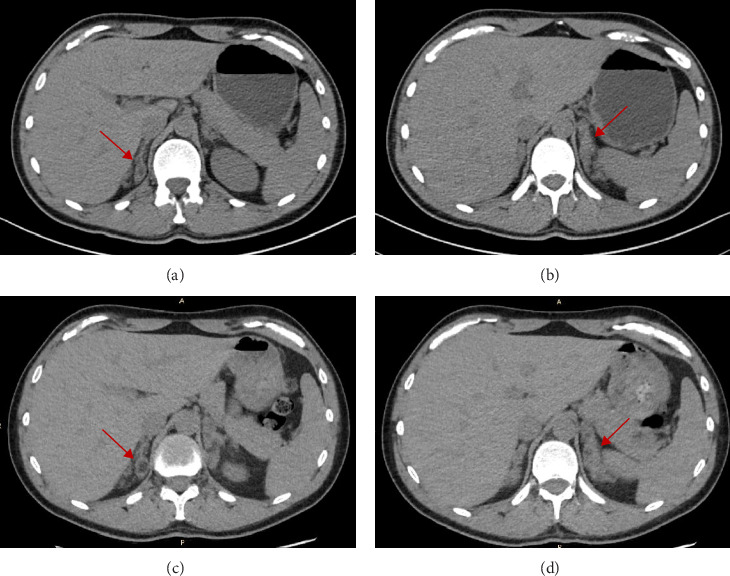

Congenital adrenal hyperplasia (CAH) due to 11-beta-hydroxylase deficiency (11β-OHD) is the second most common steroidogenesis impairment in European populations, characterized by hypertension, hypokalemia, infertility, hyperandrogenism, and genital ambiguity in females. We present the case of a biological male patient with 11β-OHD CAH who developed resistant hypertension, along with massive adrenal enlargement and testicular adrenal rests due to inadequate disease control while on dexamethasone treatment, compounded by drug interactions with his antiepileptic therapy. As the patient was reluctant to switch to a three-times-daily hydrocortisone regimen, he was transitioned to dual-release hydrocortisone, resulting in progressive improvement of most of his symptoms. This case highlights the importance of tailored therapy, particularly in rare diseases.

由11- β-羟化酶缺乏症(11 - β- ohd)引起的先天性肾上腺皮质增生症(CAH)是欧洲人群中第二常见的类固醇生成障碍,其特征是女性高血压、低钾血症、不孕症、高雄激素症和生殖器模糊。我们报告了一例患有11β-OHD CAH的男性生物学患者,他在接受地塞米松治疗期间由于疾病控制不充分而出现了顽固性高血压,并伴有大量肾上腺肿大和睾丸肾上腺衰竭,加上药物与抗癫痫治疗的相互作用。由于患者不愿改用每日三次的氢化可的松治疗方案,因此改用双释氢化可的松治疗,导致其大部分症状逐渐改善。该病例突出了量身定制治疗的重要性,特别是在罕见疾病中。